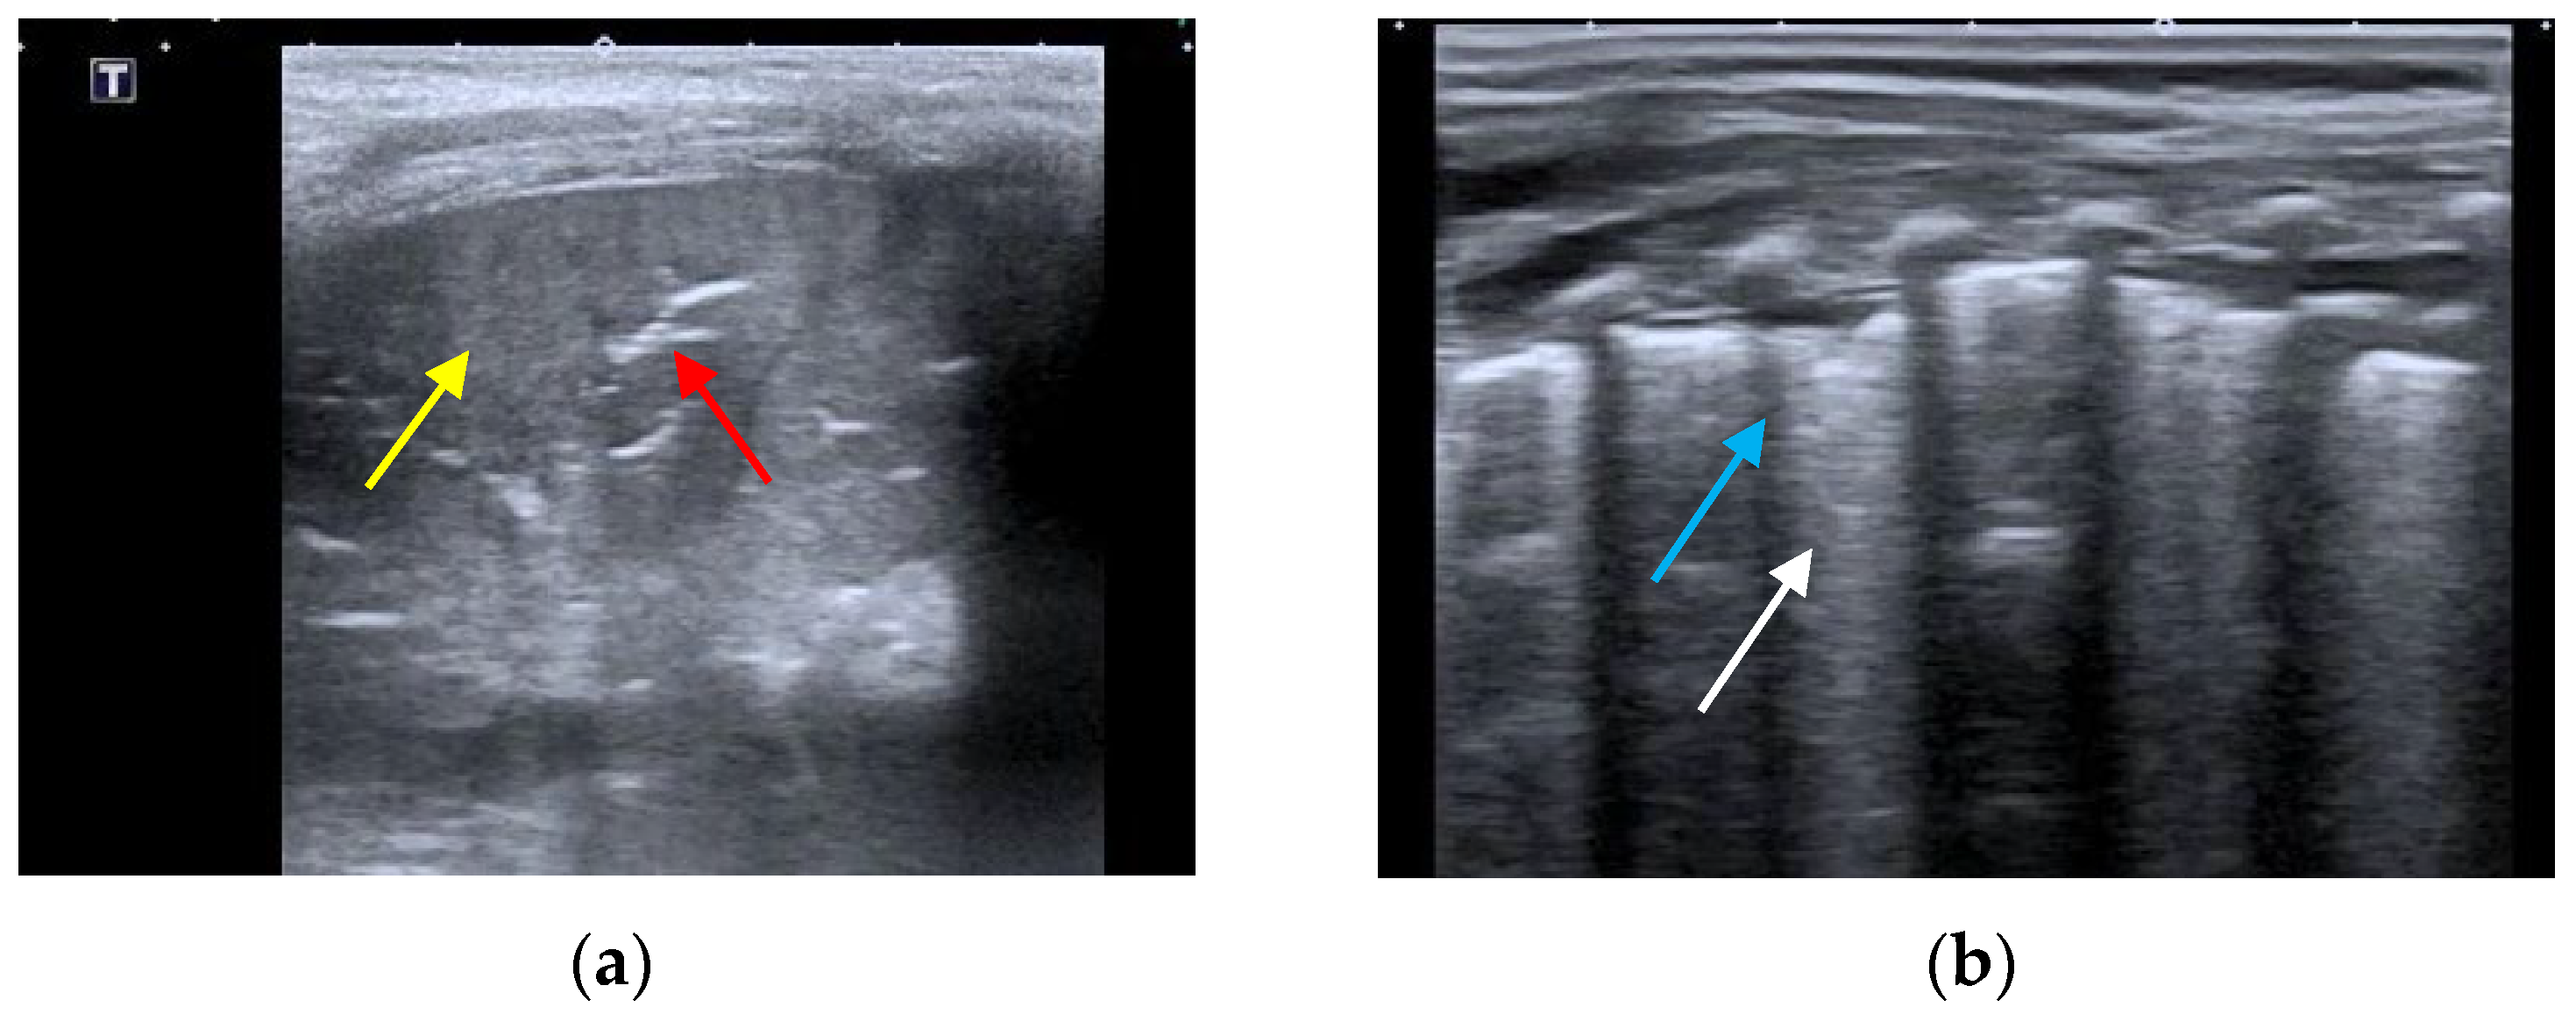

- The presence of A-lines.

- The presence of B-lines, their characteristics (short or long, spared or confluent) and their location (peri-lesional, monolateral/bilateral).

- The main lesion (consolidation): size, whether it is single or multiple, location (monolateral or bilateral). The presence of small subpleural consolidations (<1 cm).

- The presence of a bronchogram and its characteristics (air or fluid), morphology (branched or dot-like), dynamics during breathing (poorly or clearly dynamic); vascular pattern, presence of lung point and pulmonary pulse.

- The presence of lung sliding (M-mode).

- The presence and type of pleural effusion.